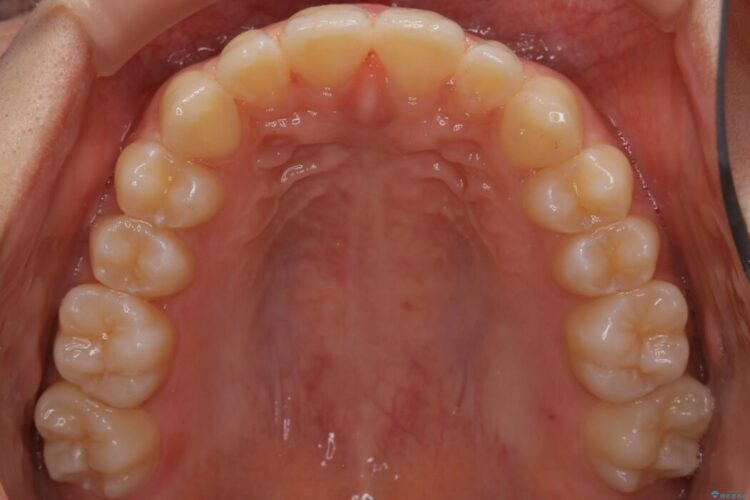

すきっ歯を改善したいとご来院された患者様です。

マウスピース14枚・期間4ヶ月で主訴であるすきっ歯を改善し、治療を終えることが出来ました。